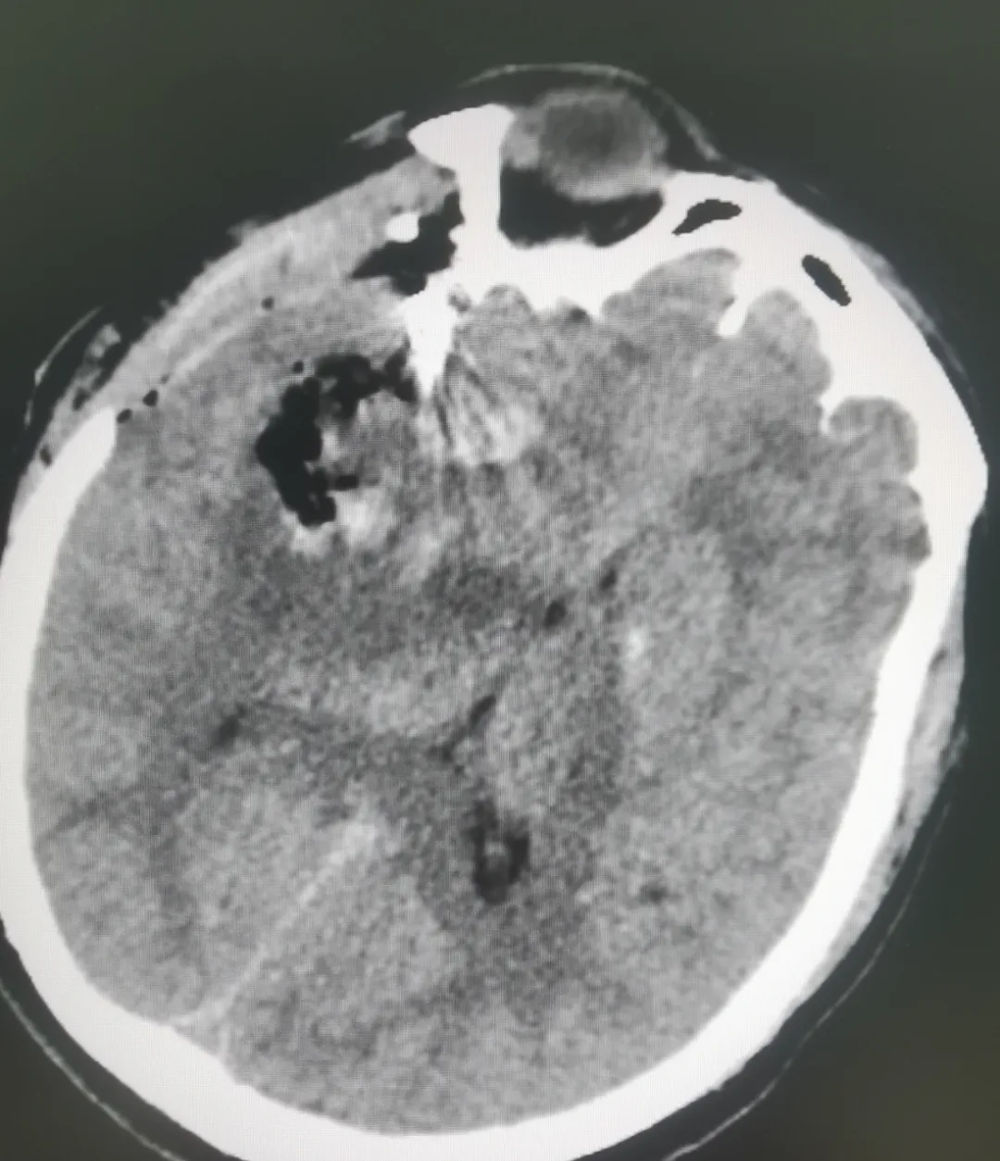

【填補縣域空(kōng)白】武寧縣總(zǒng)醫院人民醫院院區神經外科成功完成首例腦(nǎo)動脈瘤夾閉手術

近日,武寧縣總醫院(yuàn)人民醫院院區神(shén)經外科團隊順利完成了我縣首例破裂腦動脈瘤夾閉手術,患者術後情況良好,恢複(fù)效果理想。

腦動脈瘤夾閉借助高清晰顯微鏡下操作,手術難度高、風險大,以(yǐ)往(wǎng)此類患者隻能轉診(zhěn)上級醫院。人民醫院(yuàn)院區神經(jīng)外科團隊憑借紮實的(de)專業功底迎難而(ér)上,精準操作,成功拆除患者顱內"不定(dìng)時炸彈(dàn)"。這一突破填補了我縣(xiàn)在腦動脈瘤治療領域的技術(shù)空白。